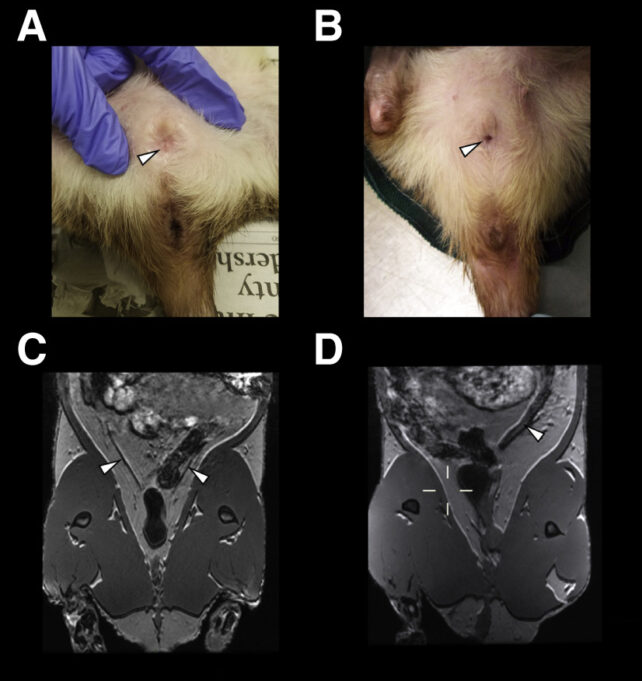

Confundidos, los investigadores observarán más de cerca y descubrirán, para horror de todos, que muchas de las ratas no solo tuvieron muy pocos hijos, sino que fecharon sus vaginas para evitar más descendencia.

En este estado morfológico, las hembras tienen un útero más pequeño y una abertura vaginal fusionada. Además, su orina tenía una composición química profundamente diferente a la de sus camaradas con aberturas vaginales normales que se reproducen activamente.